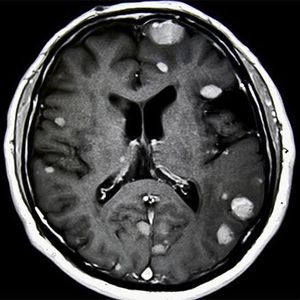

When cancer develops elsewhere in the body and spreads (metastasizes) to the brain, it’s called a secondary brain tumor, or metastatic brain cancer. Metastatic brain tumors are more common than primary brain tumors. Some cancers that commonly spread to the brain include lung, colon, kidney and breast cancers.